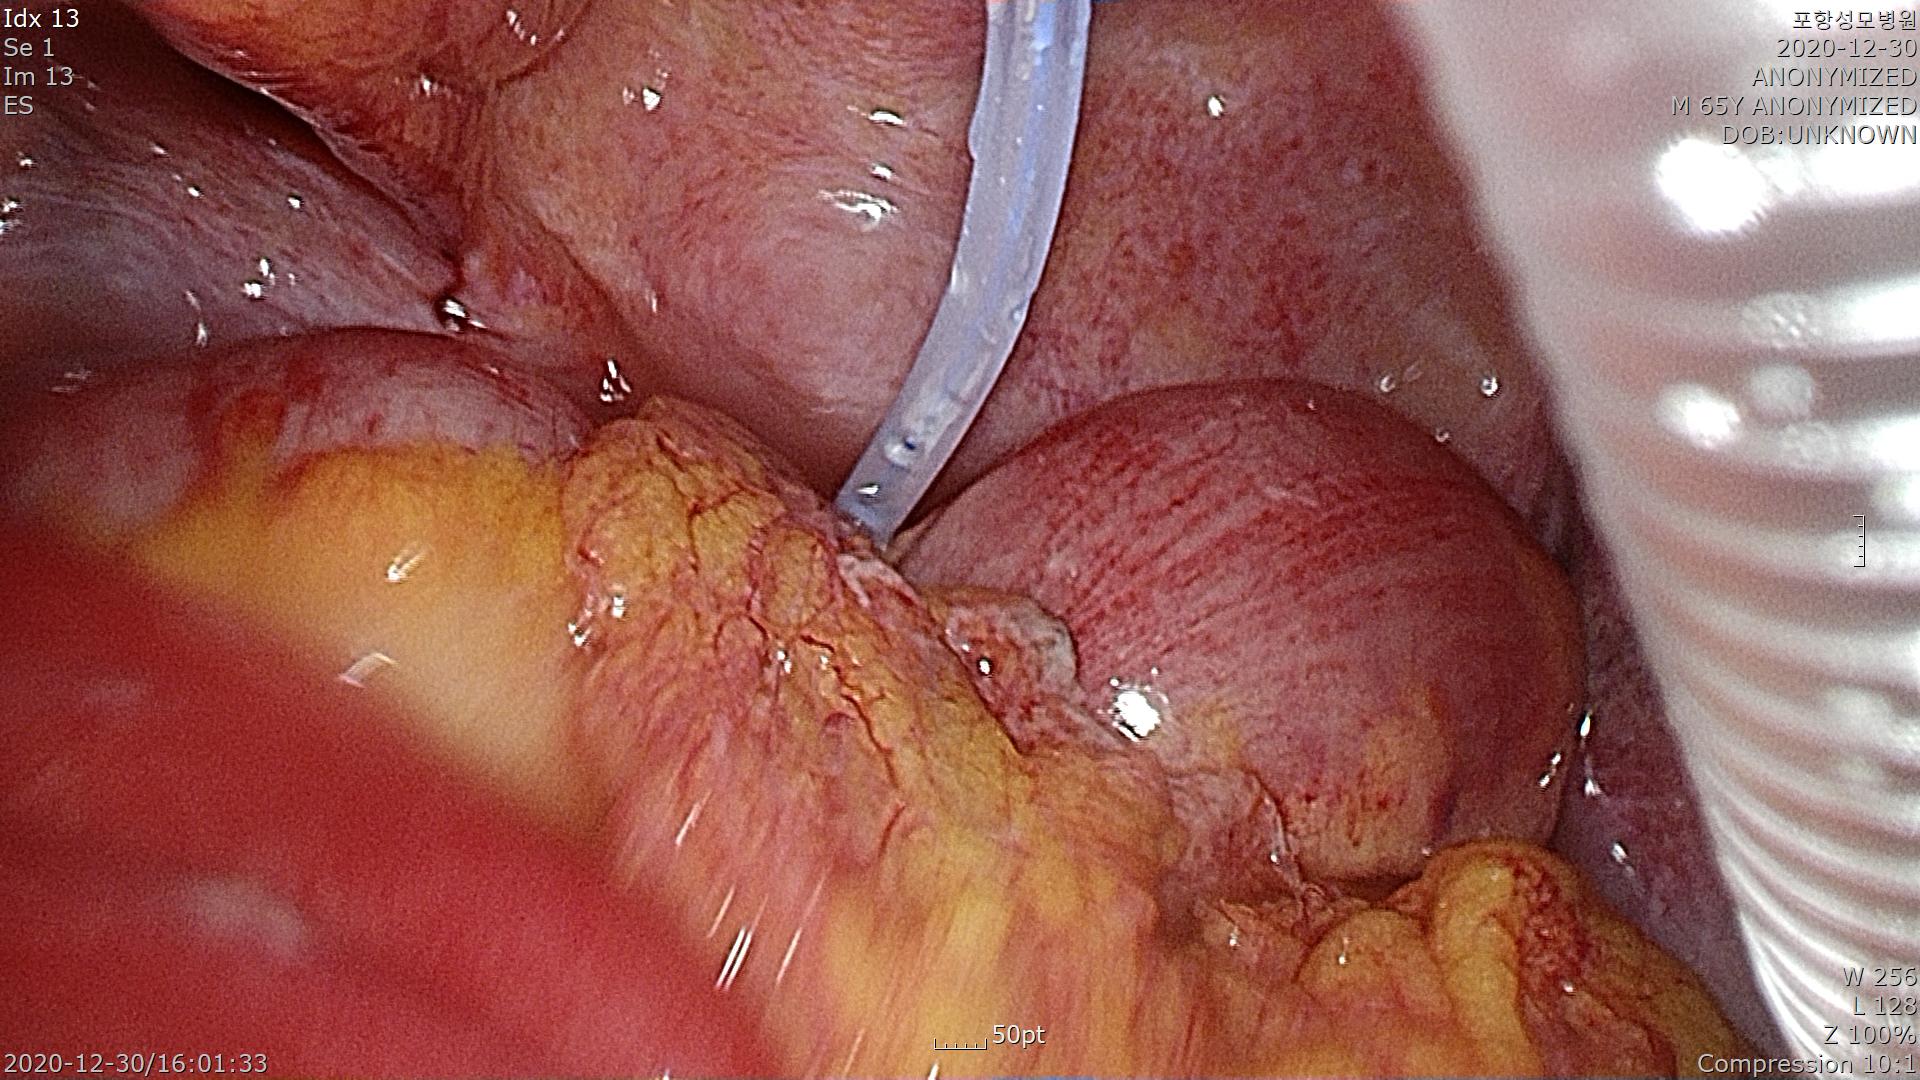

복강경으로 접근했습니다.

복강내에 충수돌기염 천공으로 인해 복막염으로 진행되었으며 복막염이 전 복강에 다 진행된 경우에 범복막염(Panperitonitis)라고 합니다.

이 환자의 경우는 범복막염입니다.

복통이 시작된지 하루밖에 되지 않았는데도 굉장히 염증이 빨리 진행된 경우입니다.

염증이 있는 대망(Greaster omentum)을 걷어내고 충수돌기를 확인합니다.

염증으로 인해 주위 조직에 유착이 되어 있고 천공부위도 확인됩니다.

충수돌기를 들어올리고 엔도루프(Endo-loop)를 이용하여 충수돌기 기저부를 결찰합니다.

충수돌기를 제거하고 파우치를 이용하여 복강밖으로 제거했습니다.